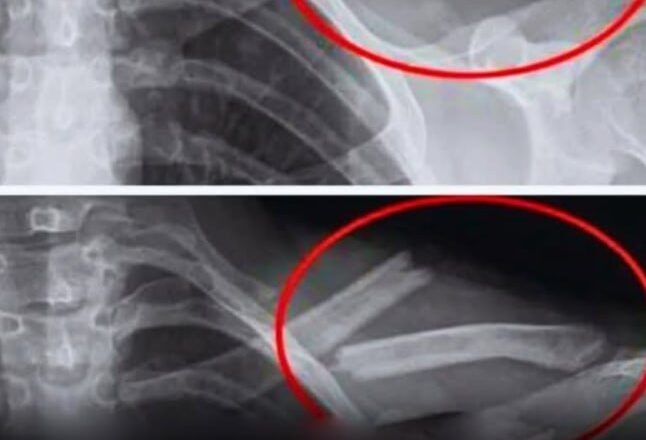

Дослідження показують, що надмірне вживання газованої води призводить до зниження щільності кісток, особливо у жінок. Іншими словами, ваші кістки слабшають… іноді без жодних симптомів, аж до перелому.

Дослідження, проведене в США за участю 2500 жінок, показало, що ті, хто регулярно пив колу, мали нижчу щільність кісток у стегнах. І вони робили це несвідомо.

Дослідження, проведене серед дівчат-підлітків, також виявило зв’язок між споживанням газованих напоїв та підвищеним ризиком переломів.